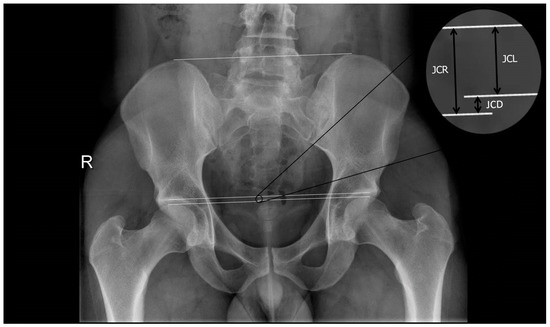

2.2. Procedure